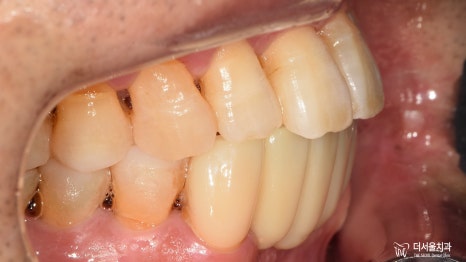

2) 측면

이쪽도 정면과 마찬가지였습니다.

구강 내에 전체적으로 번진 치주 질환 때문에

잇몸 및 치아의 상태가 좋지 않습니다.